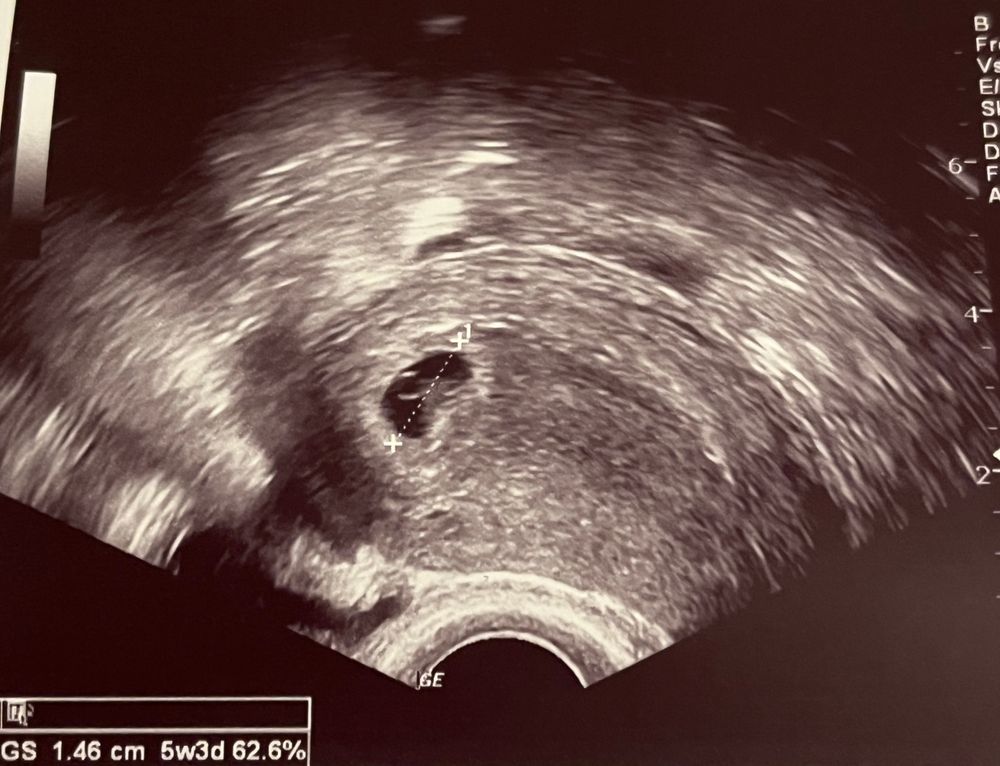

Нашли нашу крошку 🥰 5+1

Как вы себя чувствуете перед узи? Первое узи